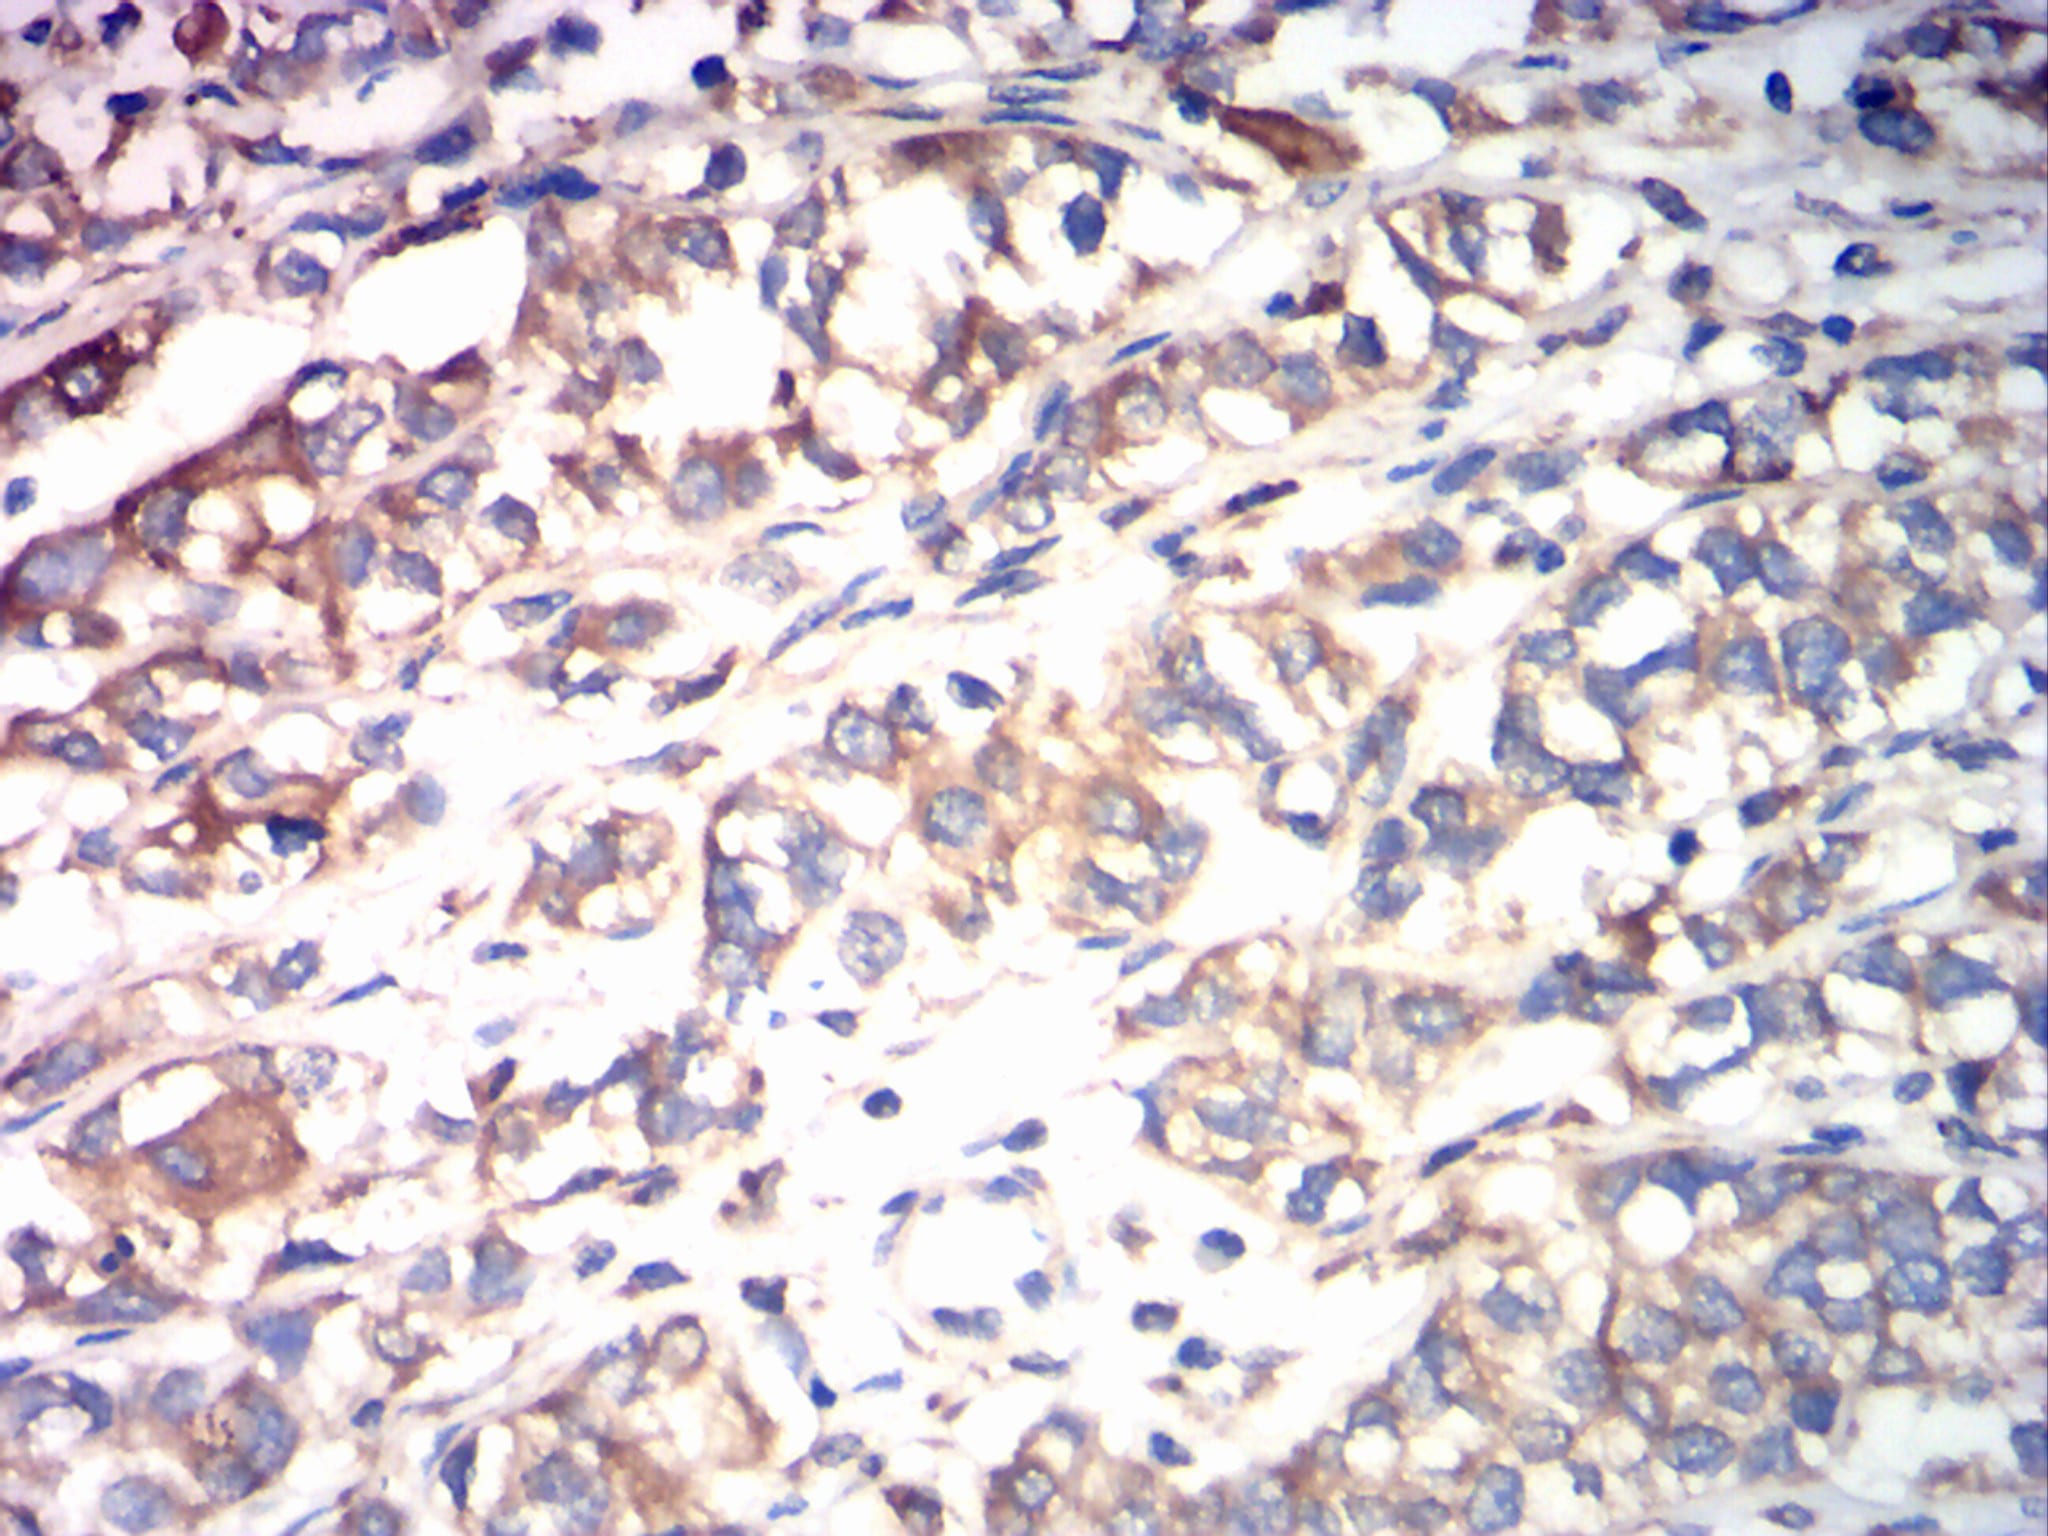

应用: WB,IHC,FCM

IHC 1/200 - 1/1000